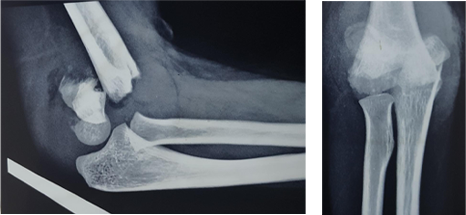

Case - 2

Supracondylar humerus fractures in Kids

Before

Pre Operative Lateral & AP view of Left elbow

After

2 month Post Operative AP and Lateral view of the left elbow